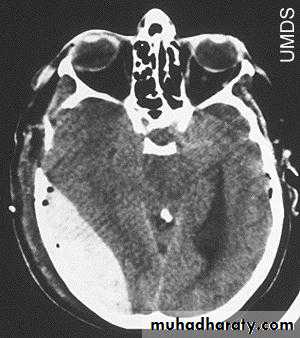

d. Subarachnoid Haemorrhage

Trauma is the commonest cause of SAH although aneurysms are the most common cause of spontaneous SAH.

Traumatic SAH is managed conservatively.